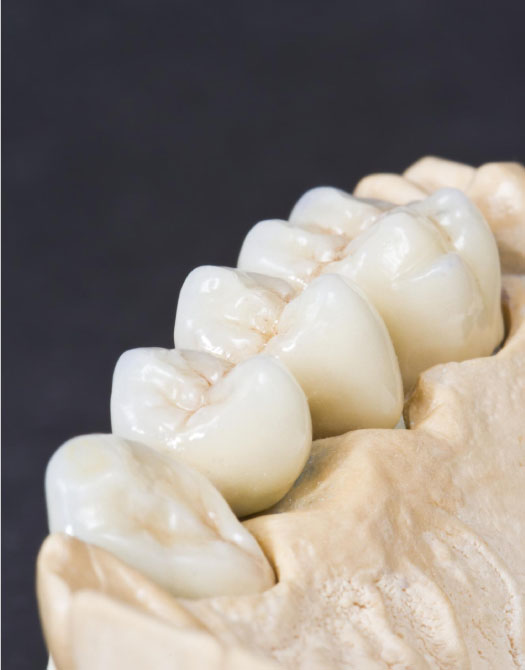

Несъемное протезирование

В стоматологической клинике «Интердентос» в Королеве несъемное протезирование выполняется с применением самых современных материалов мировых брендов. Изготовление протезов проводится в нашей собственной лаборатории, оснащенной 3D-оборудованием и инновационными технологиями.

Виды несъемных зубных протезов

1. Зубные коронки

Поврежденный зуб закрывается своеобразным чехлом, повторяющим контуры зуба. Материалами для изготовления коронок служат керамика, металл, металлокерамика, стеклокерамика, пластмасса, диоксид циркония.

2. Мостовидные протезы

Один или несколько отсутствующих зубов закрываются коронками, прикрепленными к искусственной десне. Мосты традиционные способны закрыть дефект 1-2 зуба подряд (редко 3), опираясь на соседние здоровые зубы или импланты, служащие опорами. Например, для одного искусственного зуба изготавливается несъемный протез, мост, содержащий три коронки. Две по бокам закрывают соседние зубы, используемые в качестве креплений, а посередине остается полностью искусственный зуб. Два пропущенных зуба предусматривает четыре коронки. На три удаленных зуба мосты ставятся очень редко, так как может быть сильная нагрузка на здоровые зубы.

В передней зоне лучше всего смотрится керамика, хотя и недостаточно прочная, она идеально совпадает с естественными зубами не только по оттенкам, но и по свойству светопропускания. Наиболее привлекательными после керамики, с точки зрения качества и эстетики, являются модели, состоящие из металлического каркаса (диоксида циркония) и покрытые сверху керамическим слоем.

Для жевательных и боковых зубов применяют металлокерамику.